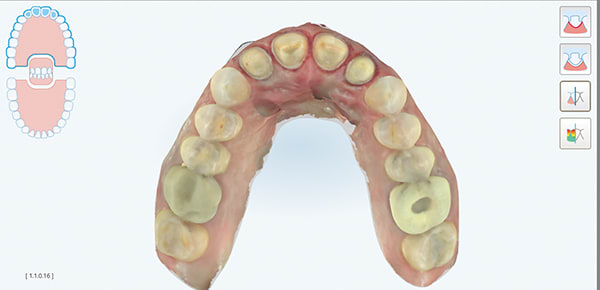

A female patient aged 57 years presented with altered passive eruption of the maxillary anterior teeth, which was diagnosed as a secondary condition to tooth erosion resulting from long-standing gastroesophageal reflux disease (GERD). Clear aligner therapy was initiated to level and align the occlusion and intrude the maxillary anterior teeth back to their original gingival position. After 18 months of poor patient compliance, improvement in tooth position was minimal and the amount of clinical overjet that was desired was not achieved. This limited the restorative armamentarium, and a decision was made to proceed with monolithic zirconia-oxide restorations. Following teeth preparation and tissue retraction, the case was impressed using an intraoral scanner (iTero® Element 2, Align Technology, Inc., itero.com). The final restorations were made of zirconium dioxide with a feldspar veneering ceramic shade 1M1 as the pressed layer on porcelain on the facials. The outcome of the case met the patient's primary concerns, achieving the lengthening and lightening of the anterior teeth that she desired. Because of the patient's continued challenges with GERD, however, she reported having difficulty with compliance related to the clear aligner therapy and whitening protocols, precluding a more ideal result. Nonetheless, the patient was pleased with her new smile and the clinician, given the challenging circumstances, was satisfied with the clinical results of the final restorations.

A key component of the zirconia-based treatment for this case was the use of an intraoral scanner for digital impressions, which allowed for clear marginal visualization, time efficiency, and a simplified impression process.

Digital impressions are an effective, predictable alternative to conventional impression techniques and may be considered as the first option for impression-taking.